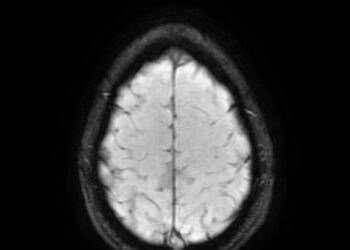

There’s a safer and smarter way. After a head injury or fall, particularly in older adults, a dangerous accumulation of...